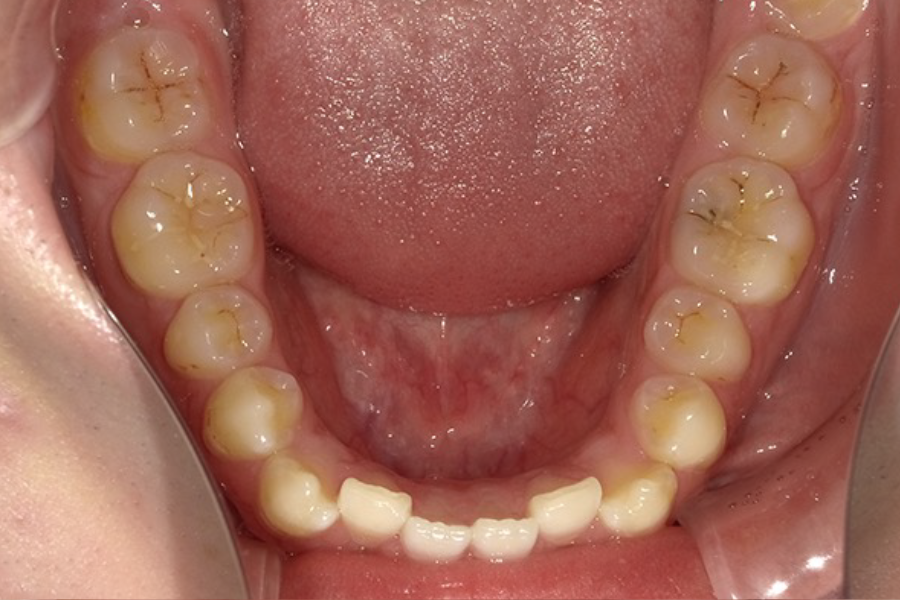

| 主訴 | 前歯の歯並びを治したい |

|---|---|

| 診断名 | 叢生 |

| 年齢 | 23歳 |

| 治療期間 | 3年1ヶ月 |

| 治療費 | 基本料金 ¥880,000 調整料 ¥5,500/月 |

| 治療内容 | 上下顎左右側第一小臼歯抜歯 マルチブラケット装置(表側) |

| 治療のリスク | 装置の見た目、歯ブラシが難しい、疼痛、口内炎、歯肉退縮、歯根吸収 |